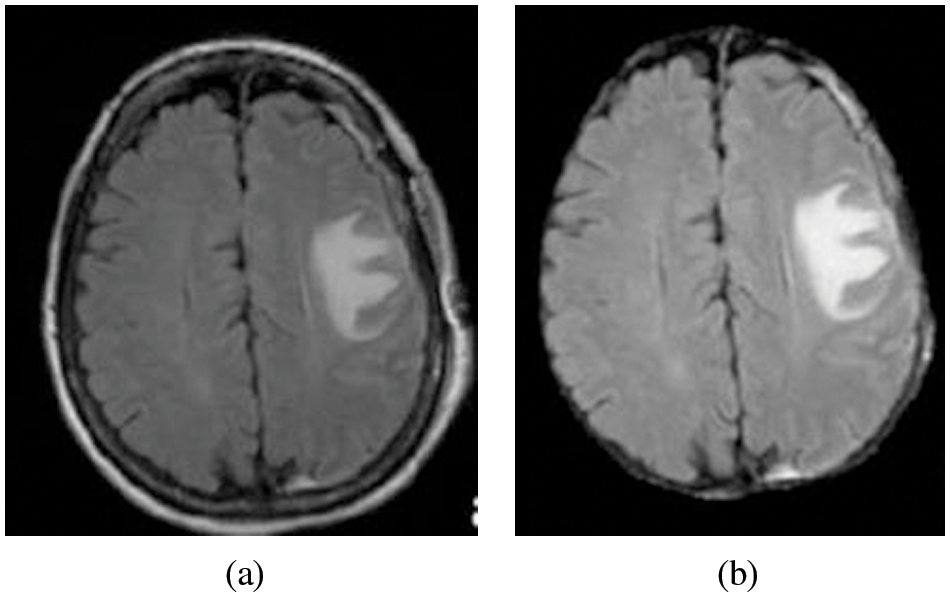

Skull stripping is a crucial practice in brain representation analysis. Skull-stripping or scalp editing to eradicate non-brain areas earlier than normalizing brains, even though this is important to all the normalization techniques [19]. Fig. 4a Pre-Processed image as the input for the skull stripping and Fig. 4b is the Image after skull stripping.

Figure 4: (a) Pre-processed image (b) Image after skull stripping